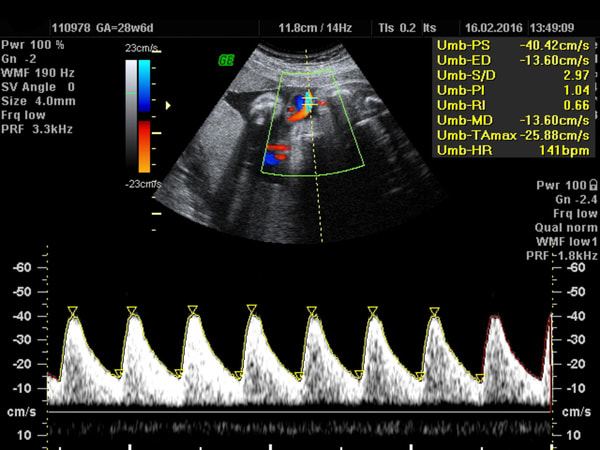

If you find your unborn baby has reduced movement, particularly in the 3rd trimester, Numi Scan can complete a well-being scan that focuses on the development of…